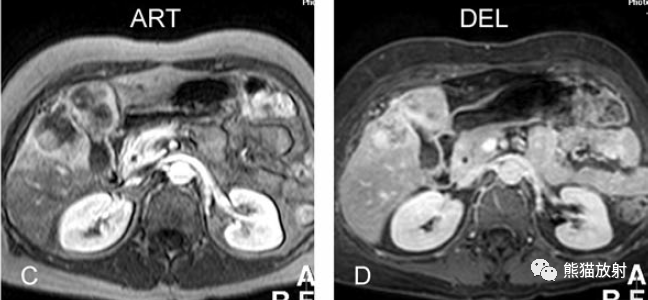

膽囊癌。A~D圖:上方層面,表現如上所述,形成腫物侵及肝臟。E、F圖:下方層面示膽囊壁不規則增厚,明顯不均質強化。

膽囊壁增厚(并肝硬化、門脈高壓、腹水)。T2WI顯示膽囊壁因水腫而光滑均勻增厚,增強延遲期顯示強化的膽囊壁(內外兩層:粘膜層和漿膜層),薄而清晰光滑。